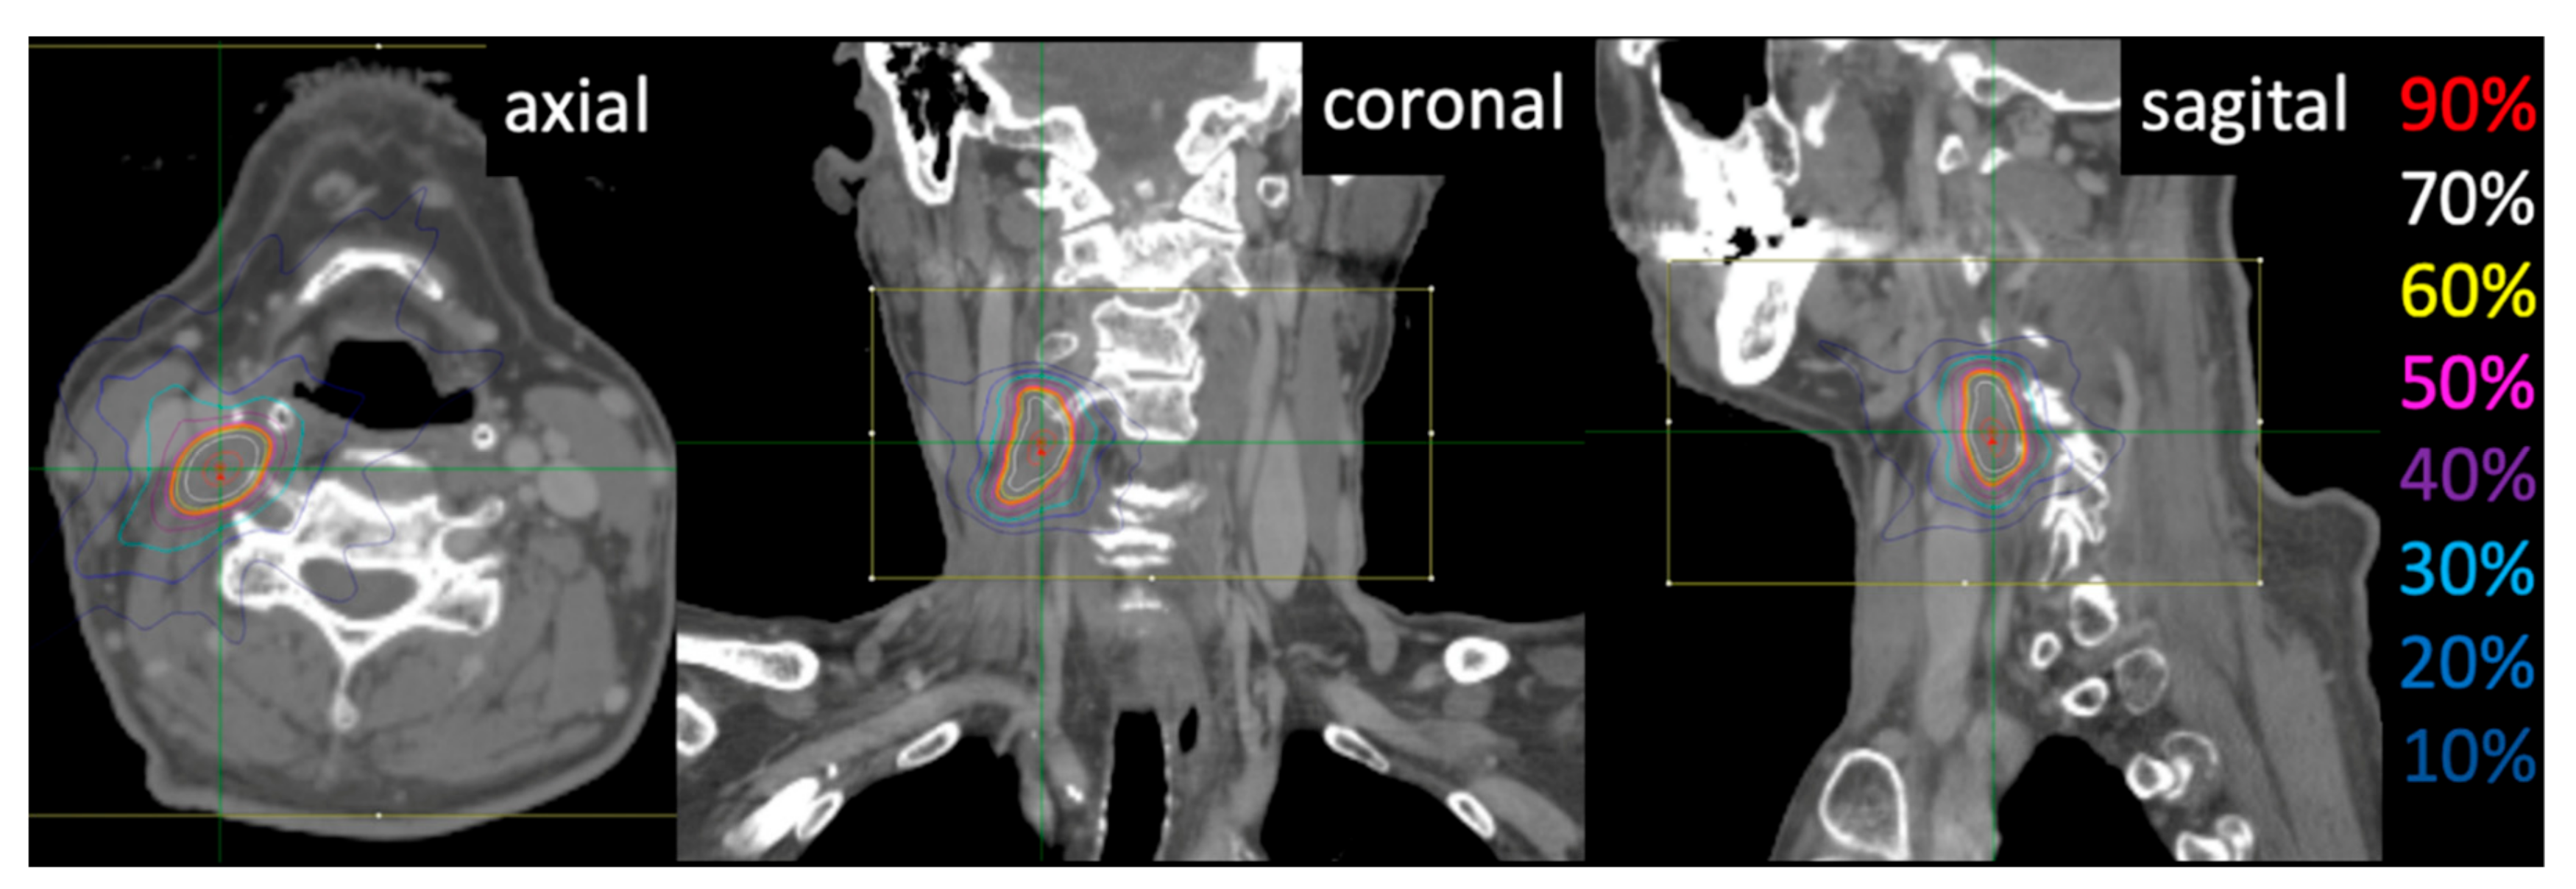

2.2. Treatment

3.3. Dose–Volume Histogram